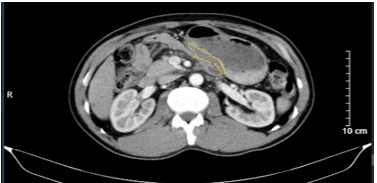

Hình 3. Hình ảnh chụp cắt lớp vi tính ổ bụng. Hình ảnh các hạch cạnh bờ cong nhỏ dạ dày, sau tiêm ngấm thuốc, hạch lớn nhất kích thước 16 x 10mm (mũi tên màu cam)

Hình 5. Hình ảnh chụp cắt lớp vi tính ổ bụng. Hình ảnh vài hạch nhỏ cạnh bờ cong nhỏ dạ dày, sau tiêm ngấm thuốc, kích thước giảm so với trước điều trị tân bổ trợ (mũi tên màu xanh lá)